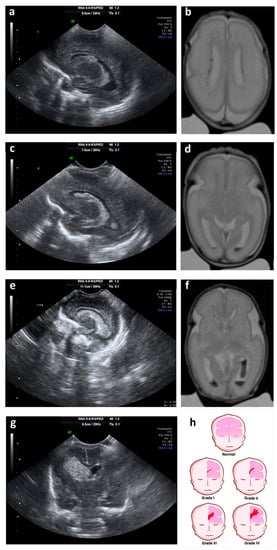

Figure 1.

Ultrasound and magnetic resonance imaging (MRI) showing different grades of GM-IVH. (a) Parasagittal cerebral ultrasound through lateral ventricles shows grade I hemorrhage; (b) T2-weighted axial MRI shows grade I hemorrhage on both lateral ventricles; (c) parasagittal cerebral ultrasound through lateral ventricles shows grade II hemorrhage; (d) T2-weighted axial MRI shows grade II hemorrhage on the left lateral ventricle; (e) parasagittal cerebral ultrasound through lateral ventricles shows grade III hemorrhage; (f) T2-weighted axial MRI shows grade III hemorrhage on the left lateral ventricle and grade II hemorrhage on the right lateral ventricles; (g) coronal cerebral ultrasound shows grade IV or periventricular hemorrhagic infarction; (h) cartoon representing ultrasound classification of the germinal matrix-intraventricular hemorrhage (GM-IVH).

Currently, grade IV is no longer considered a propagation of the original hemorrhage, but a consequence of the obstruction of the venous drainage, with a consequent venous infarction and an hemorrhage of the adjacent tissue (peri-ventricular hemorrhage infarction) [25] (Figure 1). This, among other reasons, has caused other classifications to be proposed for grading the severity of the GM-IVH [45].

Normally, the GM-IVH originates in the first days of life [15,40], and rarely occurs during birth [41]. In more than 90% of cases GM-IVH appears in the first week after birth [40], being rare the cases in which the GM-IVH occurs after the third day of life [21]. GM-IVH may spread the next days, block the venous drainage of the terminal veins affecting the adjacent parenchyma and developing ventriculomegaly by obstruction of cerebrospinal fluid (CSF) circulation [32]. Typically, GM-IVH is categorized into 4 degrees according to the severity of the GM-IVH [42,43]. Grades I and II lesions are known as mild GM-IVH, and grades III and IV lesions are considered severe GM-IVH [44].

- Grade I: hemorrhage localized only in the subependymal GM (caudo thalamic groove).

- Grade II: intraventricular hemorrhage without ventricular dilation.

- Grade III: intraventricular hemorrhage with ventricular dilation.

- Grade IV: parenchymal hemorrhage that corresponds to periventricular venous infarctions with hemorrhagic evolution [5].